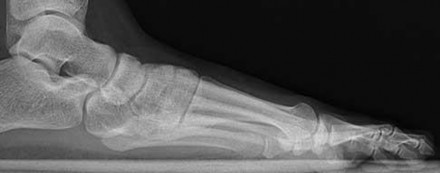

Figure 10 is an anteroposterior pelvis radiograph of an 82-year-old man who had right hip pain that began 2 weeks ago but has since resolved with use of over-the-counter nonsteroidal anti-inflammatory drugs (NSAIDs). Currently he has no pain. Examination of his hip shows decreased internal rotation and minimal pain at the extremes of motion. What is the most appropriate treatment at this point?

13

The radiograph shown is consistent with Paget disease of the bone. It demonstrates classic findings of widened lamellae and disorganized sclerotic and lytic areas. The cause is not clearly defined, but may be linked to a viral infection and subsequent alterations of osteoblastic and osteoclastic activity. Most patients are asymptomatic, and Paget disease is often found incidentally on radiographs. In this case, the patient’s symptoms likely were caused by hip arthritis, but Paget disease can cause diffuse bone pain in some cases. Considering the patient’s mild and short-term symptoms, observation and NSAID use is most appropriate. An MRI scan or biopsy is indicated if sarcomatous transformation is suspected, but this condition is rare and is associated with a substantial, unrelenting increase in pain. SPEP and UPEP are tests for multiple myeloma, of which the radiographs show no signs.